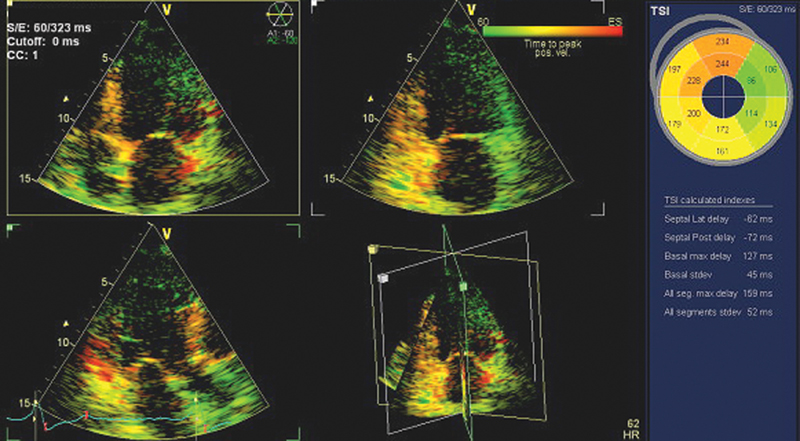

فحوصات تشخيصية لبعض امراض القلب والشرايين التاجية